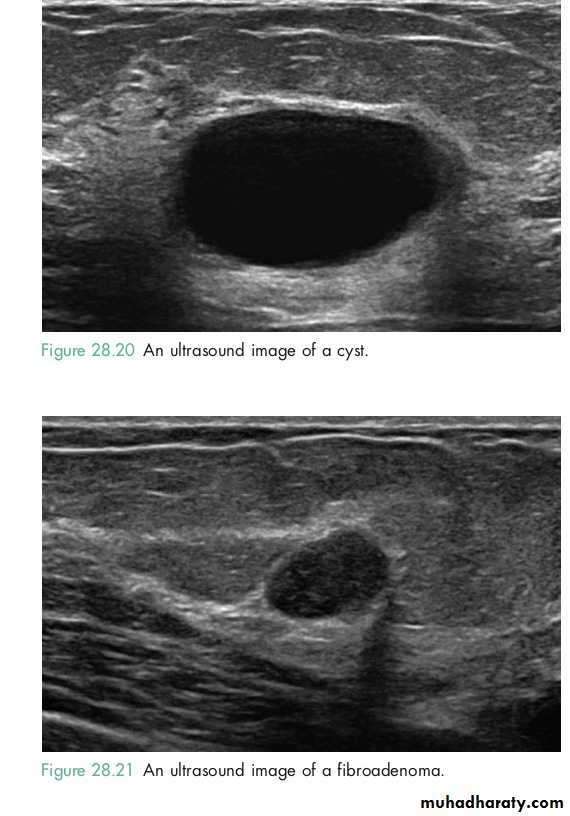

Ultrasound is particularly useful in young women with dense breasts in whom mammograms are difficult to interpret, and in distinguishing cysts from solid lesions.